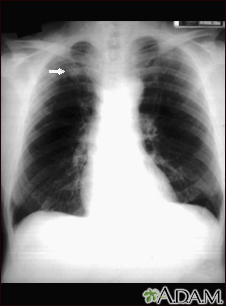

Pulmonary nodule - front view chest x-rayBackPulmonary nodule - front view chest x-rayThis x-ray shows a single lesion (pulmonary nodule) in the upper right lung (seen as a light area on the left side of the picture). The nodule has distinct borders (well-defined) and is uniform in density. Tuberculosis (TB) and other diseases can cause this type of lesion. E-mail FormEmail ResultsName:Email address:Recipients Name:Recipients address:Message: